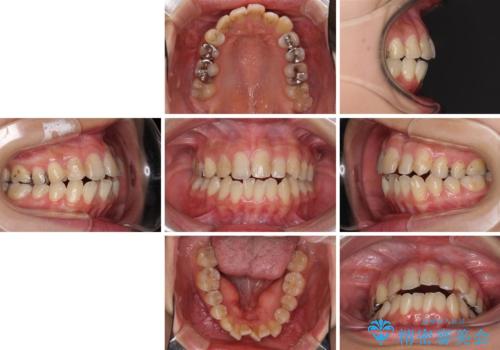

- 中学生の時に矯正治療をしたものの、後戻りを気にして来院された患者様です。

骨格的に下顎が右側に変位しているため、左右の咬み合わせを理想的なものに改善することはできませんが、インビザラインにて歯列を整えることとしました。

骨格的なズレによる左右差は改善できませんでしたが、上下の正中を極力合わせるようにすることができました。